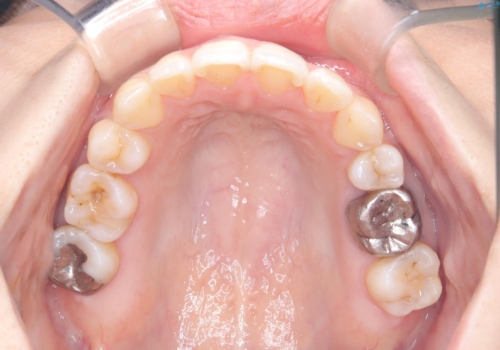

【ワイヤー矯正】口元を下げたい、下の歯の凹凸を無くしたい

- 主訴:口元を下げて前突感を無くしたい、下の歯の凹凸も無くしたい

右側第二小臼歯、左側第一小臼歯、下顎両側第一小臼歯を抜歯しワイヤ-矯正を行いました。

骨格的顎の変位を認めたため、顔貌に対しピッタリ上下の歯の正中を合わせることは難しいと説明し、上下左右計4本小臼歯を抜歯しワイヤー矯正治療を行いました。